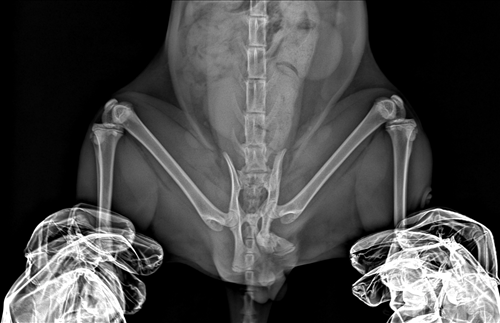

8개월 남아 코숏

최근 입양한 길냥이가 며칠간 대변을 못봐 진료를 봤습니다.

엑스레이 상 골반골절 의심 진단을 받고​​​​​​

현재 글과 첨부해주신 글만으로는 수술 가능 여부를 판단하기가 매우 어렵습니다. 특히 엑스레이상 이미 유합이 진행된(회복된) 상태로 보여 수술을 하게 된다면 의도적으로 재골절을 만들어 정렬을 다시 잡아야 하기 때문에, 이 경우 단순 골절 수술과는 난이도와 위험도에 차이가 납니다.

수술 가능 여부를 결정하려면 정밀 평가를 진행해 유합 상태와 변위 정도, 협착 정도, 신경/연부조직 평가, 직장 내가 평가도 해봐야 알 수 있습니다. CT 검사, 직장 조영 검사 등이 가능한 동물병원에 내원하셔서 상담을 받아보시는 것을 추천드립니다.